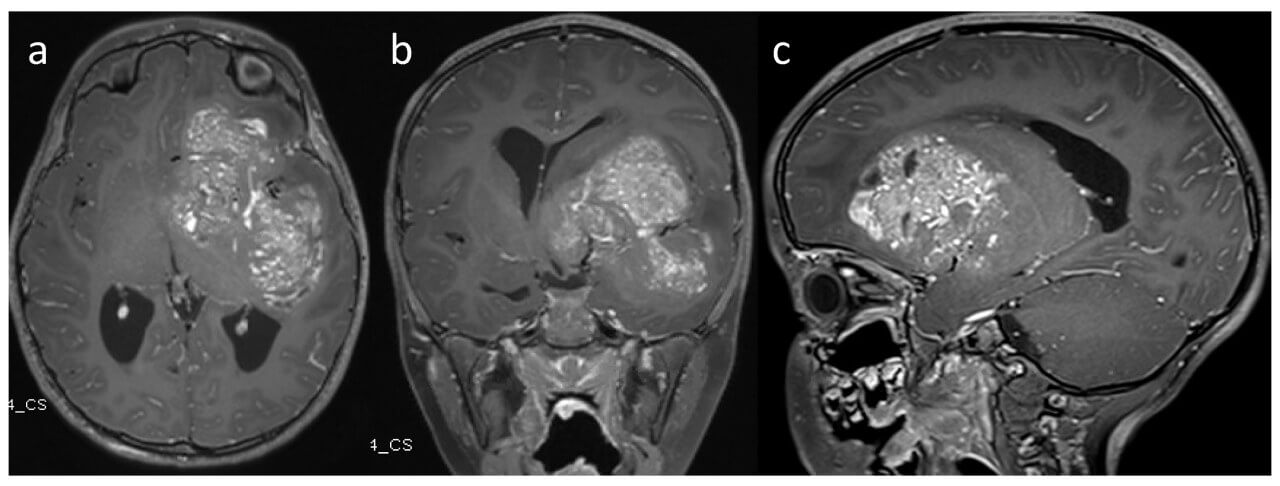

- Metastases of diverse tumors in the brain. Infection of the cerebral tissue with metastases of distant tumors is no less dangerous than the development of the primary neoplasm. MRI-guided laser therapy with the help of Visualase™ system offers the chance to destroy the smallest loci of the unwanted tissue [3].

The increase in the incidence of brain metastases is directly related to the improvement in the effectiveness of modern oncological treatment of primary malignant tumors, which leads to an increase in the life expectancy of patients and, accordingly, to a greater number of secondary lesions of the central nervous system. In this context, thermal ablation is considered a safe and minimally invasive alternative to traditional treatment methods for carefully selected patients.

The Visualase™ system has proven effectiveness in the treatment of various types of tumors, including brain tumors. The use of MRI-guided laser ablation for brain tumor treatment with the Visualase system combines the advantages of this approach with high precision, controllability, and minimal invasiveness, which makes the method particularly valuable in complex clinical cases [5].